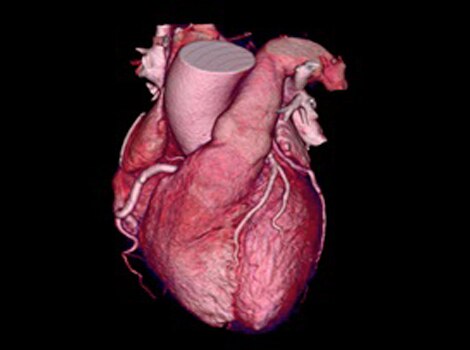

Revolution CT & CardioGraphe7

Achieve one-beat, whole heart acquisition for imaging or comprehensive cardiac assessment with or without beta blockers at any heart rate.8

Revolution CT & CardioGraphe3

Achieve one-beat, whole heart acquisition for imaging or comprehensive cardiac assessment with or without beta blockers at any heart rate.4 Read More

Revolution CT & CardioGraphe4

Achieve one-beat, whole heart acquisition for imaging or comprehensive cardiac assessment with or without beta blockers at any heart rate.5